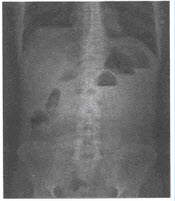

男性,43岁,腹痛、呕吐,停止排便排气1天,行腹部立位X线平片检查,如下图

有关肠梗阻的CT表现,

不正确

的是()

A:梗阻远近端肠管直径有明显差异

B:闭袢型肠梗阻时可见"鸟喙征(beaksign)"

C:动力性肠梗阻可见小肠大肠的弥漫性充气扩张

D:绞窄性肠梗阻肠壁可出现分层改变

E:乙状结肠闭袢性扭转时扩张的乙状结肠呈马蹄状,内有两个较大液平

F:小肠内只要有液气平面就可诊断肠梗阻